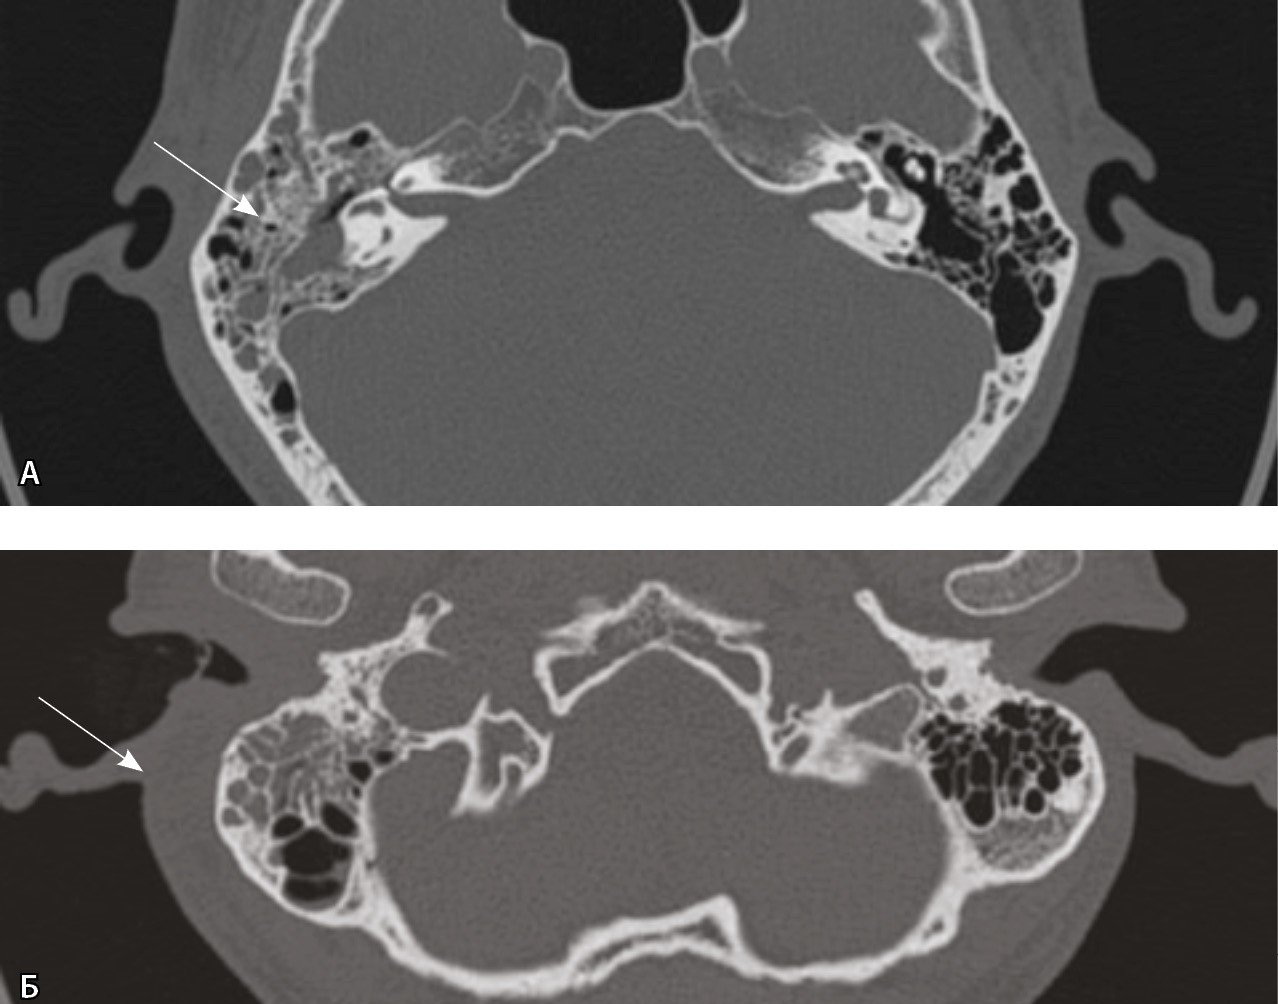

Выполнена КТ височных костей, а затем КТ шеи с контрастом. При КТ височной кости справа определялся пневматического типа строения сосцевидный отросток, практически все ячейки которого были выполнены субстратом. При этом деструктивных изменений как костных стенок ячеек, так и кортикального слоя достоверно не определено (рис. 2).

Рис. 2. Компьютерная томография височной кости, аксиальный скан, костное окно. А – в клетках сосцевидного отростка, антруме и барабанной полости справа определяется содержимое (стрелка); Б – асимметричное утолщение парааурикулярных мягких тканей справа (стрелка)

При КТ основания черепа и шеи до и после внутривенного болюсного введения йодсодержащего контрастного препарата (в рекомендуемом согласно инструкции по применению препарата объеме и с рекомендованной скоростью введения) и дальнейшем анализе сканов в абдоминальном окне начиная с уровня наружного основания черепа справа имелось явно определяемое асимметричное утолщение мягких тканей и уплотнение клетчаточных пространств. Однако на фоне утолщенных мягких тканей в режиме обычной визуализации дополнительных жидкостных образований, требующих хирургического вмешательства, не обнаружено. Так как исследование выполняли на компьютерном томографе Philips iQon Spectral CT (Philips, Нидерланды), был проведен анализ моноэнергетических изображений с низкими энергиями. Это позволило выявить в толще измененных мягких тканей на уровне сосцевидного отростка, в парафарингеальном пространстве низкоконтрастные сообщающиеся жидкостные образования – скопления гноя, которые на обычных изображениях не определялись и могли быть пропущены врачом-рентгенологом (рис. 3).

Рис. 3. Компьютерная томография шеи, венозная фаза. Фронтальная реконструкция и аксиальный скан. А, Б – обычный режим, мягкотканное окно; В, Г – моноэнергетическое изображение 40 кеВ на том же уровне: виден субпериостальный абсцесс вдоль латеральной поверхности верхушки сосцевидного отростка (стрелки), не определяемый в обычном режиме

Заключение по проведенному исследованию: правосторонний мастоидит, субпериостальный абсцесс на уровне верхушки правого сосцевидного отростка (абсцесс Бецольда), флегмона шеи справа.